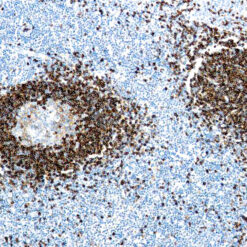

This MAb recognizes human 17-26kDa protein, which is identified as cytokine TNF-α (Tumor Necrosis Factor-alpha). Monomeric human TNF-α is a 157 amino acid protein (non-glycosylated) with a reported molecular weight of 17 kDa and can be expressed as a free molecule, also TNF-α is generated as a precursor form called transmembrane TNF-α can be expressed as a cell surface type II polypeptide consisting of 233 amino acid residues molecular weight 26 kDa. TNF-α is an important cell-signaling component of the immune system. It is a protein secreted by LPS stimulated macrophages, and causes tumor necrosis when injected into tumor bearing mice. TNF-α is currently being evaluated in treatment of certain cancers and AIDS Related Complex.

| Positive Control Tissue | Colon, Histiocytoma, Pancreas |